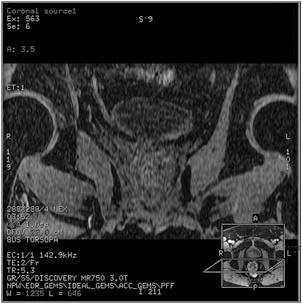

Figure 6. Example of: Coronal reformat of sagittal LAVA-Flex scan with ARC Slice = 2 (R/L). Coil coverage in R/L is much larger than the scan coverage in R/L direction resulting in noise amplification due to parallel imaging technique.